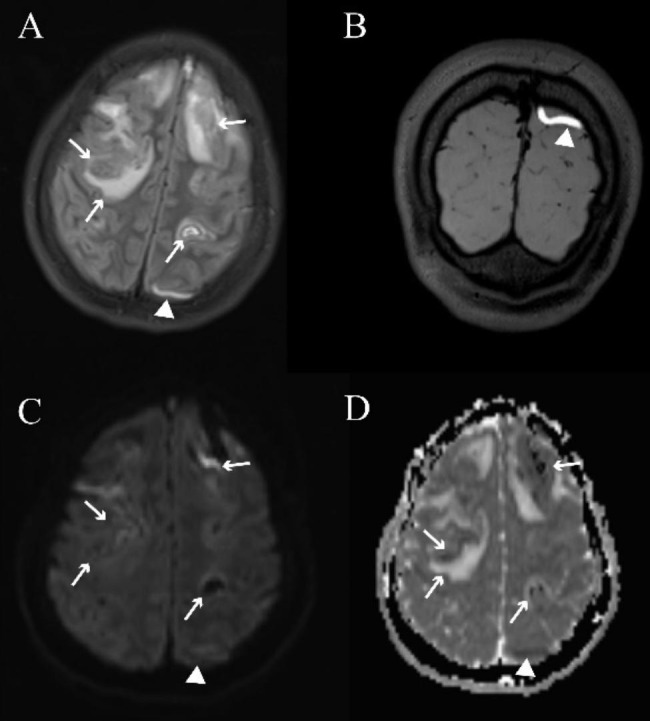

Fig. 1.

Typical images of cortical vein thrombosis on conventional magnetic resonance imaging and 3D-T1-SPACE scans in a 17-year-old female patient with cerebral venous sinus thrombosis. The fluid-attenuated inversion recovery (FLAIR, A) image shows a cord-like hyperintensity (white arrowheads, representing a subacute thrombosis) of the left cortical vein, which presents as restricted diffusion (white arrowheads) on the diffusion-weighted image (DWI, C) and apparent diffusion coefficient map (ADC, D), consistent with the thrombosed cortical veins on 3D-T1-SPACE (white arrowheads, B). Venous infarction and parenchymal hemorrhage can be observed as mixed signals on FLAIR, DWI, and ADC scans (white arrow)